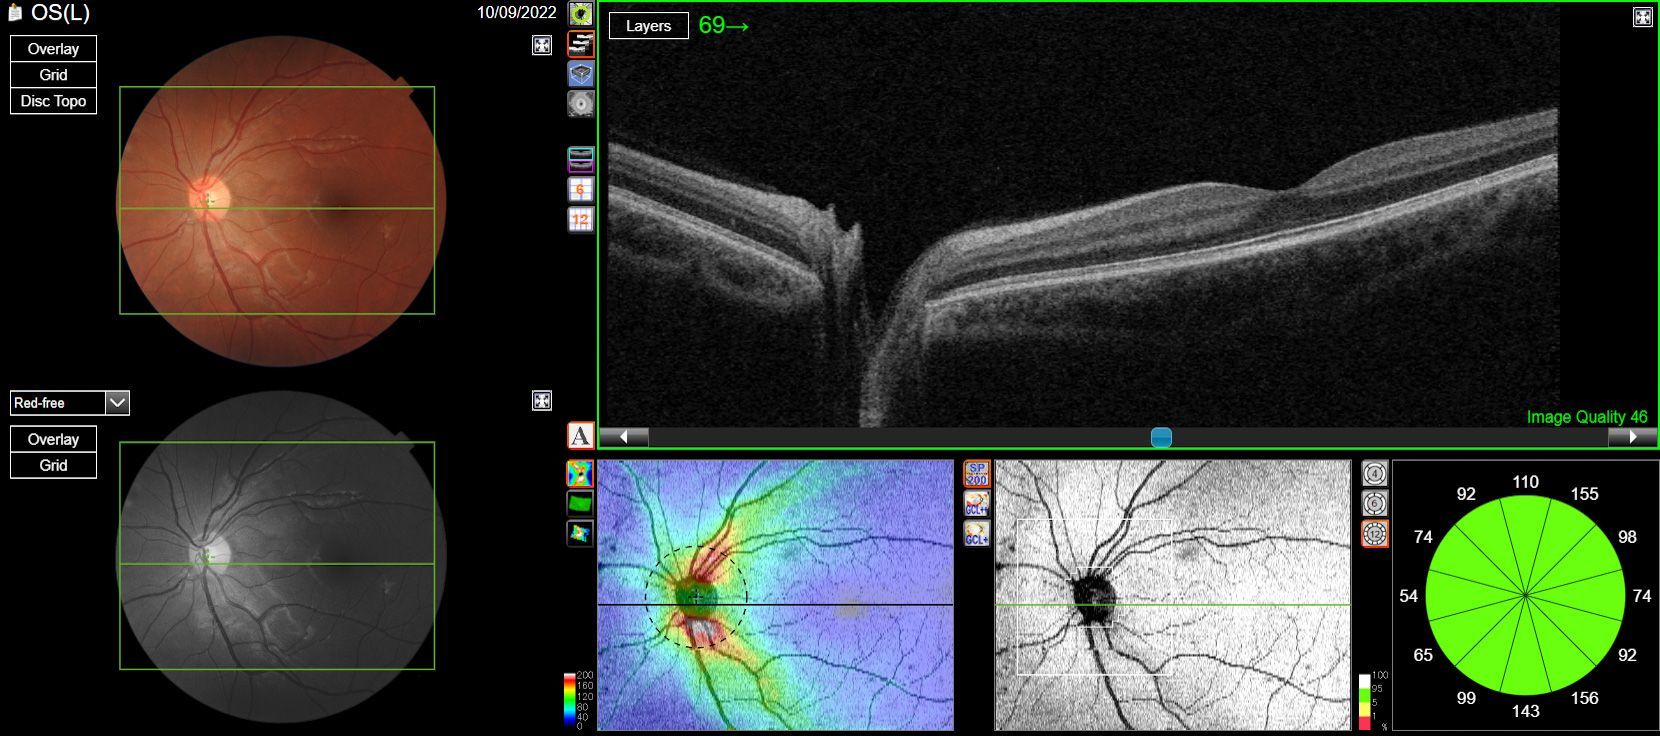

OCT (Optical Coherence Tomography) is technology that allows us to take a deep dive into the underlying health of the eyes. Conventional ocular health check methods only show us the surface level eye health, OCT however enables us to view the underlying layers in the back of the eye that would otherwise be invisible to the naked eye. This is particularly useful when dealing with conditions such as glaucoma and macular degeneration as we're able to detect signs earlier, which can make managing conditions and preventing long term vision problems a lot easier.

One of the many benefits of Advanced Eye Examinations and OCT technology, is the ability to build a portfolio of your ocular health. This means that in years to come, we're able to look back at through previous OCT scans/results and compare them, observing any changes in tremendous detail. Continually monitoring these potential changes in this level of detail means we are able to pick things up quicker and can make resolution/treatment that much simpler. You can rest assured that your eye care is looked after and monitored for not only the present day, but the long term also.